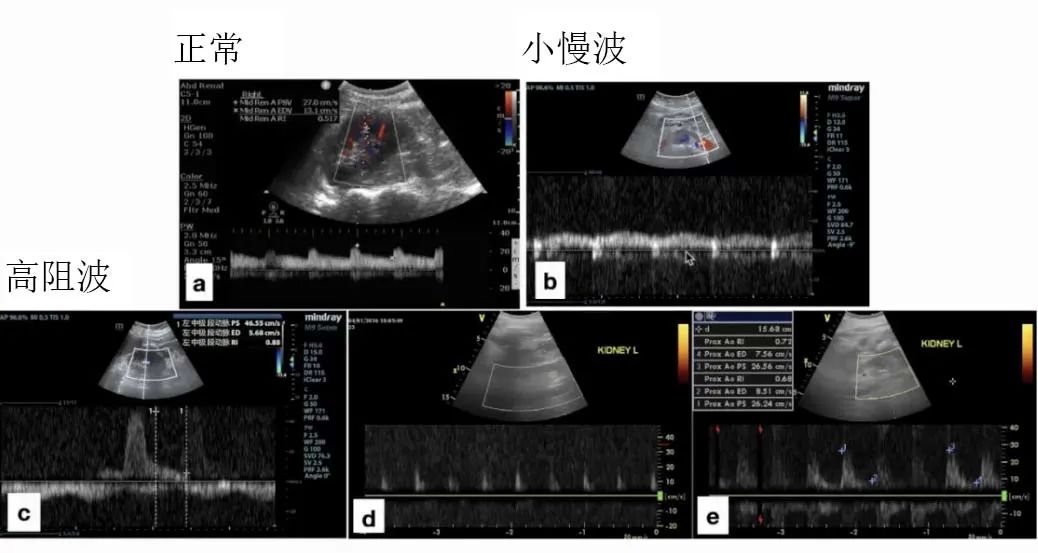

针对ICU患者,观察肾内叶间动脉十分重要,因为它负责支配远端微循环的血管。正常肾动脉血流频谱应为低阻型,表现为收缩早期频谱上升陡直,后缓慢下降, 其正常肾脏动脉阻力指数(RRI)应在0.58(±0.05)~0.64(±0.04)。 异常肾动脉血流频谱主要包括高阻血流、小慢波。

RRI在临床应用时,可以反映病理生理机制、识别病因、帮助制定治疗策略。 RRI的影响因素有很多,其中血管顺应性是影响肾血管阻力的关键因素。

肾内小慢波较为少见,因为肾脏本身有非常好的自我调节能力,当灌注减少,肾血管首先会收缩。因此,虽然血量减少,但血管内径更细,血液流速反而可能增快。高阻波表现为肾舒张期血流速度明显降低,峰值速度根据血流量呈现降低或增多的改变。

肾动脉血流频谱不同波形超声图